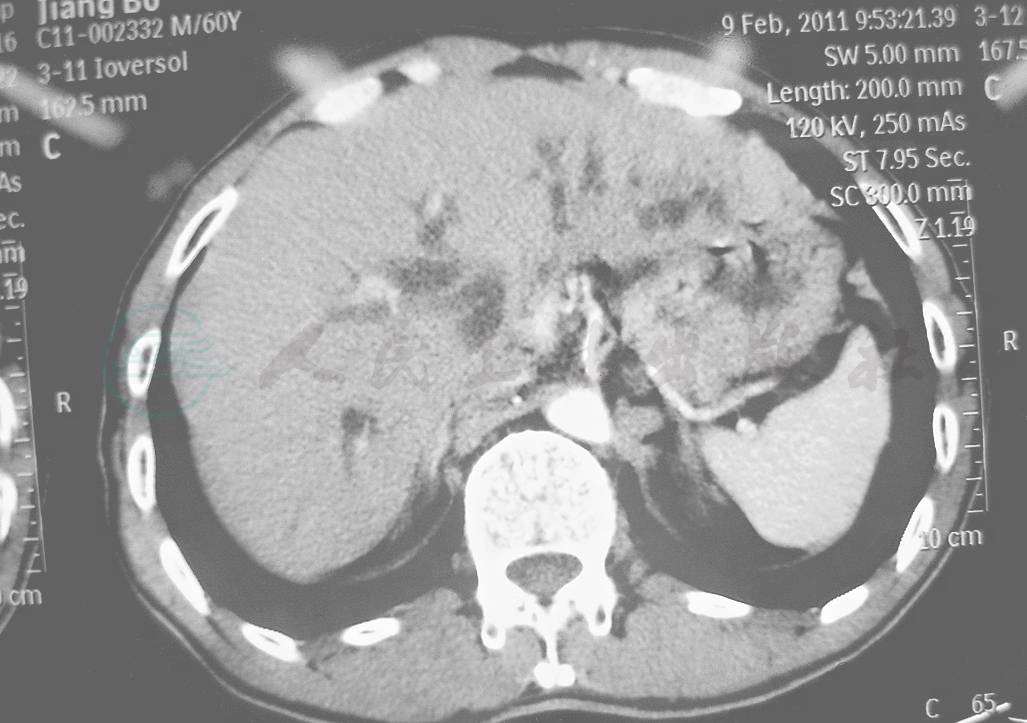

增强扫描(动脉期):左肝内胆管“狗尾征”(+)(图2)。

图2 CT增强扫描(动脉期)示左肝内胆管“狗尾征”(+)